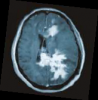

Primary central nervous system lymphoma: Case report

Jose Garcia R. MD , Marco Mejía T. MD, William Anicama L. MD